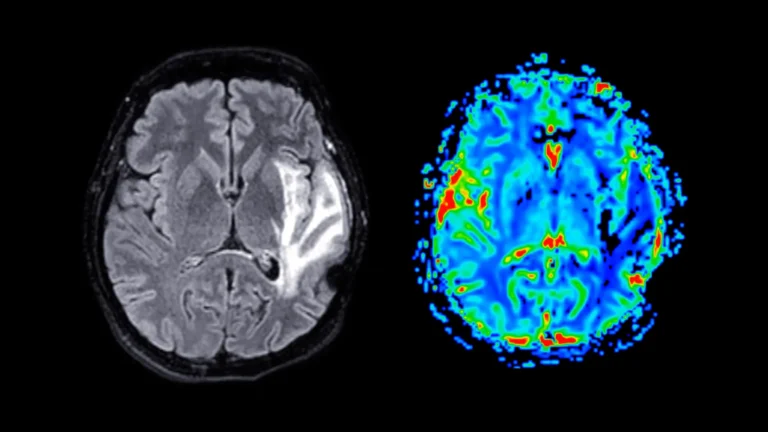

Um extenso estudo realizado no Reino Unido, envolvendo mais de 165.000 pessoas com demência, revelou que o medicamento risperidona está associado a um aumento do risco de AVC em todos os grupos de pacientes. Os resultados desafiavam suposições anteriores que sugeriam que alguns pacientes poderiam ser candidatos mais seguros para a medicação. Em vez disso,…